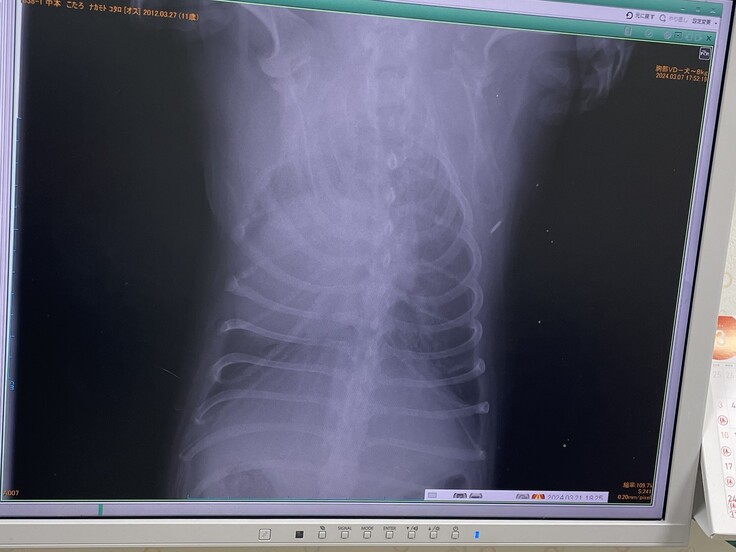

▼レントゲン

去年2月より心臓が大きくなっており肺・呼吸器が圧迫されていて咳が出る状態

(普通のわんこは真ん中に心臓があるが、こたろは左に寄っていて、

これが生まれつきなのかはわからないとの事)

※かかりつけ病院の診断書(病院名・住所は隠してあります。先生の掲載許可済み)